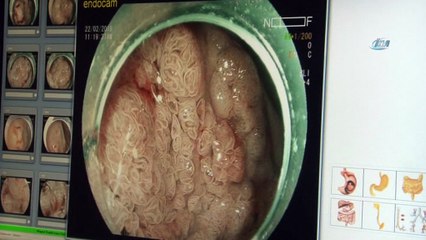

Acıbadem Bursa Hastanesi, Genel Cerrahi Uzmanı Prof. Dr. Abdullah Zorluoğlu, Kanser üzerine soruları yanıtlıyor;br br "Kolon kanserine karşı hangi önlemleri almak gerekir?"br br Acıbadem Sağlık Grububr www.kanserekarsiyalnizdegilsiniz.